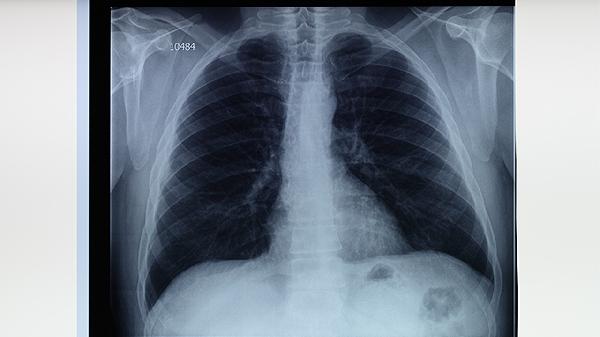

肺结核治愈的标准包括临床症状消失、影像学病灶稳定、痰涂片及培养连续阴性。达到临床治愈后,体内残留的休眠菌多数会被免疫系统逐渐清除,复发概率较低。但极少数情况下,当免疫力严重下降时,休眠菌可能重新激活导致复发。治愈后仍需定期复查胸部影像学,监测病灶变化。